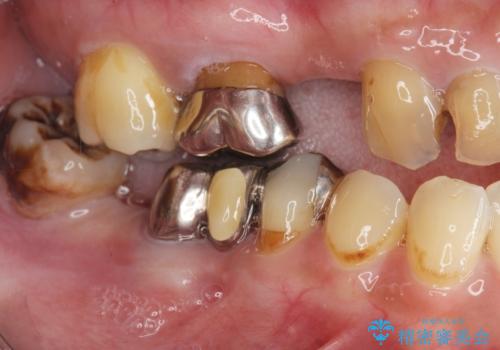

- 「歯の見た目が悪く、奥歯も噛みづらい、しっかりと全体的に治療したい。」と全顎的な治療を希望され来院されました。

虫歯・感染根管・予後不良歯・欠損・不正咬合、複合的な問題を一つづつ丁寧に解決し、将来に渡り不安のない口腔内環境にすべく全体的な総合治療を行っていきます。